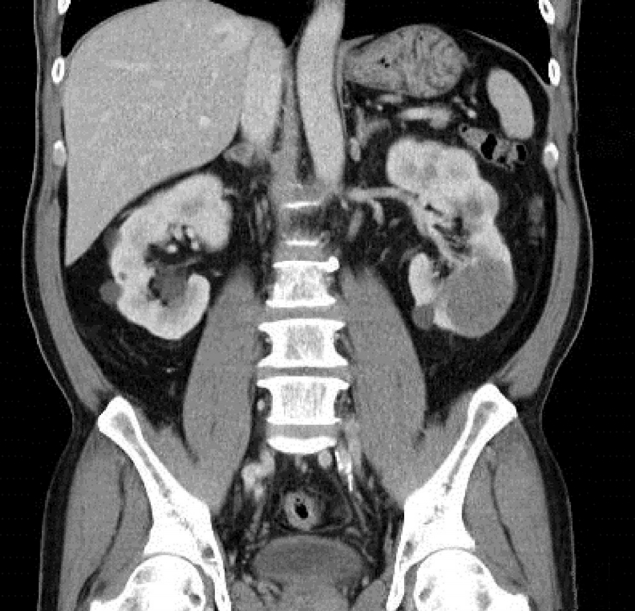

A 60-year-old male patient underwent laparoscopic radical nephrectomy for a 6.3-cm-sized solid mass in the lower pole of the left kidney, under general anesthesia. His body parameters were weight 84.2 kg, height 175.3 cm, and body mass index 27.4 kg/m2. He had hypertension and diabetes for 20 years, gout for 10 years, and dyslipidemia for an unknown period. Each disease was treated with daily medication including ARB valsartan 80 mg (Diovan; Novartis Pharma Schweiz, Rotkreuz, the Switzerland), adrenergic beta-antagonist carvedilol 25 mg (Dilatrend; Chong Kun Dang Pharmaceutical Corp., Seoul, Korea), calcium channel blocker amlodipine 5 mg (Orodipine; Dong-A ST, Seoul, Korea), oral antidiabetic agent glimepiride 25 mg (Glimel, Dong-A ST), and xanthine oxidase inhibitor allopurinol 100 mg (Zyloric; Samil Co., Seoul, Korea). He had been a smoker and had a drinking history. On radiologic evaluation, both kidneys of the patient were filled with multiple cysts in addition to the mass in the lower pole of the left kidney (Figure 1).

Figure 1.

Abdominal and pelvic spiral computed tomography shows an approximately 6.3-cm-sized probable enhancing solid lesion in the lower pole of the left kidney and multiple variable-sized cysts in both kidneys.